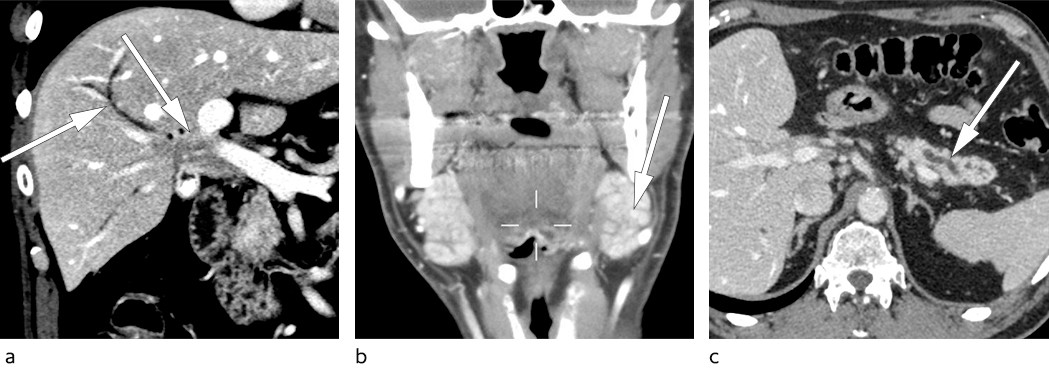

Pasienten kom til poliklinisk konsultasjon dagen etter mottatt henvisning. Det hadde nå gått åtte måneder siden symptomdebut. Ved undersøkelse var blodtrykket 150/105 mm Hg og pulsen 73 slag/min. Pasienten hadde lymfadenopati med 4 × 3 cm store glandler på begge sider av halsen og en mindre lymfeknute i venstre lyske, som ble vurdert til å sannsynligvis være patologisk. Allmenntilstanden fremstod lett redusert. Pasienten ble utredet med CT-lymfomprotokoll, som viste en stor, diffus oppfylning i leverhilum som vokste inn i ductus hepaticus communis (figur 1a). Glandlene på halsen ble beskrevet som fyldige submandibulære spyttkjertler og var ikke metastasesuspekte (figur 1b). Pankreas var atrofisk som ved tidligere MR-undersøkelse (figur 1c). Funnet ga sterk mistanke om et perihilært kolangiokarsinom.

Seks dager etter overflytning ble det utført utvidet høyresidig leverreseksjon med hepatikojejunostomi. Postoperativt utviklet pasienten leversvikt med påfølgende iskemisk nekrose i gjenværende levervev. Tilstanden ble bedømt som meget alvorlig med liten sjanse for spontan bedring. Reseksjonspreparatet ble derfor undersøkt som cito-prøve i tilfelle tilstanden skulle være benign og dermed tillate transplantasjon. Histologisk prøve fra leverhilum viste ikke tegn til malignitet, men lymfoplasmacytære infiltrater og rikelig med eosinofile granulocytter. Immunhistokjemisk undersøkelse påviste overvekt av IgG4-positive plasmaceller og forhøyet IgG4/IgG-ratio på over 0,4 (figur 2). Serum-IgG4-prøve ble tatt postoperativt og var forhøyet på 6,0 g/l (0,03–2,01 g/l). Funnene var forenelige med IgG4-relatert sykdom.